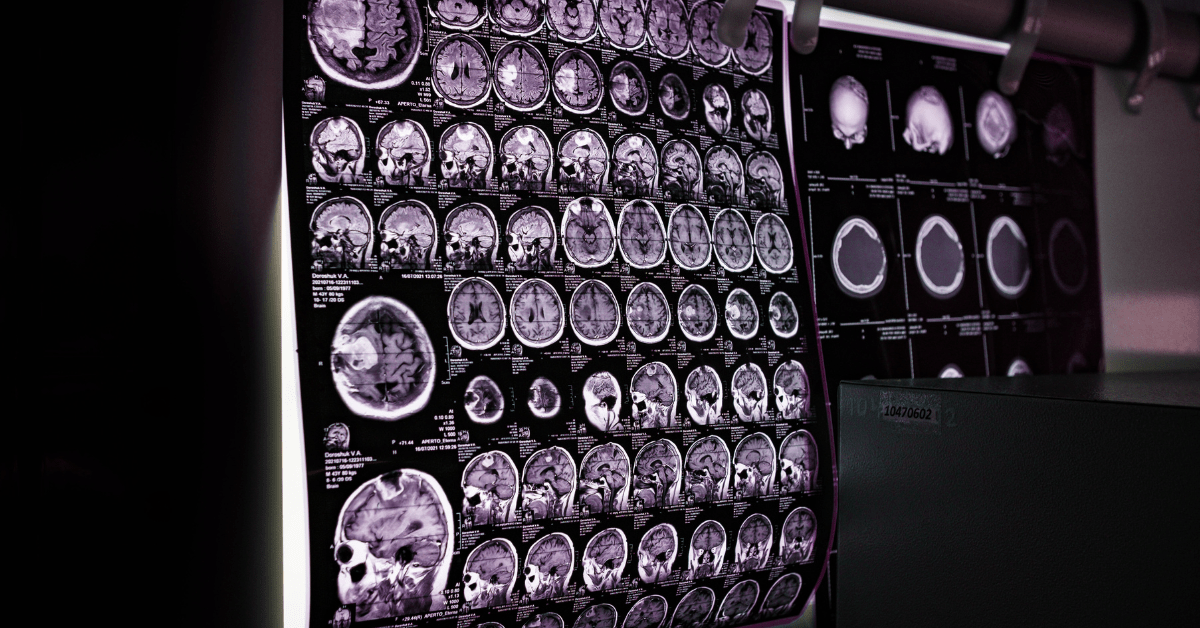

How PACS integration improves diagnostic turnaround times in hospitals

Picture Archiving and Communication Systems (PACS) have long been the backbone of medical imaging. Yet, without seamless...